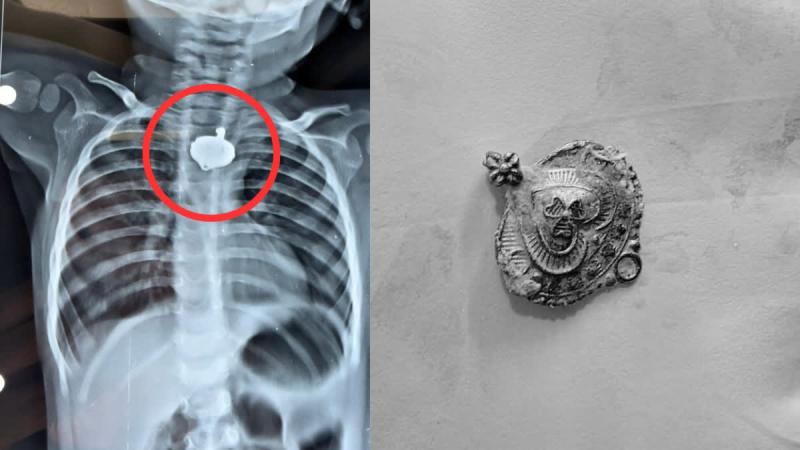

बड़वानी: रविवार को जिला अस्पताल में एक बेहद संवेदनशील और हैरान करने वाला मामला सामने आया. जब 9 माह के एक बच्चे के गले में मंगलसूत्र फंसा हुआ देखा गया. घटना उस समय सामने आई जब ग्राम करी निवासी नरसिंह वास्कले अपने पुत्र विवान को लगातार सर्दी-खांसी की शिकायत पर बच्चों के डॉक्टर के पास लेकर पहुंचे. बच्चे का एक्स-रे कराया गया तो उसकी आहार नली में कोई धातु दिखी.

जब उपचार के दौरान बच्चे का एक्स-रे करवाया गया, तो रिपोर्ट सामने आते ही डॉक्टर भी चौंक गए. एक्स-रे में शिशु के गले में धातु जैसी आकृति दिखाई दे रही थी. तुरंत मामले को गंभीरता से लेते हुए उसे जिला अस्पताल के ईएनटी रोग विशेषज्ञ डॉ. अनुपम बत्रा के पास भेजा गया. डॉ. बत्रा ने बच्चे की स्थिति की गहन जांच की. जिसके बाद बच्चे को बेहोश कर सटीक तकनीक और सावधानी से गले से मंगलसूत्र को सफलतापूर्वक बाहर निकाल लिया गया. चिकित्सकों के अनुसार अब बच्चा पूरी तरह खतरे से बाहर है.

डॉ. अनुपम बत्रा ने बताया कि "ये बच्चा पिछले डेढ़ महीने से सर्दी-खांसी से परेशान था. जिसके बाद उसके परिजन डॉक्टर के पास गए और बताया कि बच्चे को बार-बार सर्दी-खांसी हो रही है. जब बच्चे का एक्स रे कराया गया, तो पाया गया कि आहार नली में धातु जैसी कोई चीज फंसा है. बच्चा चुकी मात्र 9 महीने का था, इसलिए बेहोशी कर धातु को निकाला गया. जब धातु निकाला गया तो पता चला कि यह मंगलसूत्र है. जिसको लेकर बच्चे के पिता ने पुष्टी की है कि यह मंगलसूत्र गणेश चतुर्थी के बाद से गुम था. यानी करीब डेढ़ महीने से बच्चे के गले में मंगलसूत्र फंसा था."